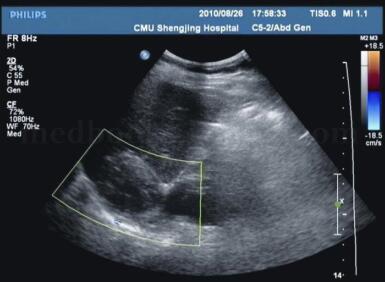

患者女,56岁,以“发现右肾上腺占位3天”为主诉入院。查体:T:36.6℃,P:76次/分,R:16次/分,BP:140/83mm Hg。患者双肾区无叩痛,双侧输尿管走行区未及明显压痛,膀胱区无明显隆起,未及包块,无压痛叩诊无浊音(图1、图2)。

图1 肾脏三维彩超:右肾上腺区见5.2cm×3.9cm实性肿物,边界清,内呈低回声。双肾位置正常,右肾大小约9.9cm×4.5cm,形态规整,皮髓质界限清晰,集合系统未见分离。右肾区未见明显占位性病变。左肾大小约9.9cm×4.5cm,形态规整,皮髓质界限清晰,集合系统未见分离